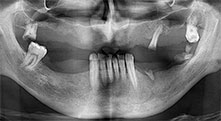

Bratu: Wir nutzen die Instrumente routinemäßig für die Entnahme von Knochenblöcken und das Spalten von Kieferkämmen. Weiterhin osteotomieren wir mit den Piezomed B6/B7 retinierte Zähne und entfernen nicht erhaltungsfähige Implantate. Alles Indikationen, bei denen es auf tiefe, saubere Schnitte ankommt.

Bratu: Wir augmentieren im seitlichen Unterkiefer gern mit der Sandwich-Technik. Dabei wird ein Knochendeckel mit der Piezosäge präpariert und das krestale Fragment mit Mikroschrauben fixiert. Dazwischen platzieren wir eine Mischung aus autologem Knochen und xenogenem Knochenersatzmaterial. Das funktioniert sehr zuverlässig. Bei Kieferkammspaltungen im Unterkiefer sollten Sie nie auf ausreichend dimensionierte vertikale Schnitte verzichten. Sonst kann der Knochen leicht frakturieren.

Bratu: Ich halte Piezo für einen großen Sprung nach vorn für die Oralchirurgie. Die Technik macht Knochenpräparationen sicherer und leichter. Man verliert wenig Knochen, zum Beispiel bei Extraktionen. In der ästhetischen Zone ist dies sehr wichtig, vor allem wenn eine Sofortimplantation geplant ist. Auch für Weichgewebe ist Piezochirurgie ein Sicherheitsgewinn: Membranverletzungen in der Kieferhöhle sind im Prinzip Geschichte, ebenso Nervverletzungen bei Knochenblockentnahmen. Es gibt auch Daten, die geringere postoperative Schwellung und Beschwerden zeigen. Übrigens lassen sich mit Piezochirurgie auch sehr gut Kieferhöhlensepten präparieren. Nicht zuletzt profitieren unsere Patienten von der schonenden Arbeitsweise dieser Technik.